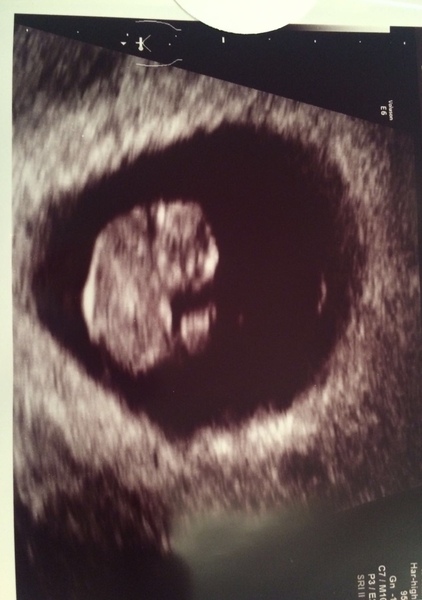

LaBelleSausage · 21/01/2019 20:57

This was DS at 8+2. We could see a surprising amount!

I’m booked in again for an early scan at what I think will be 7+5